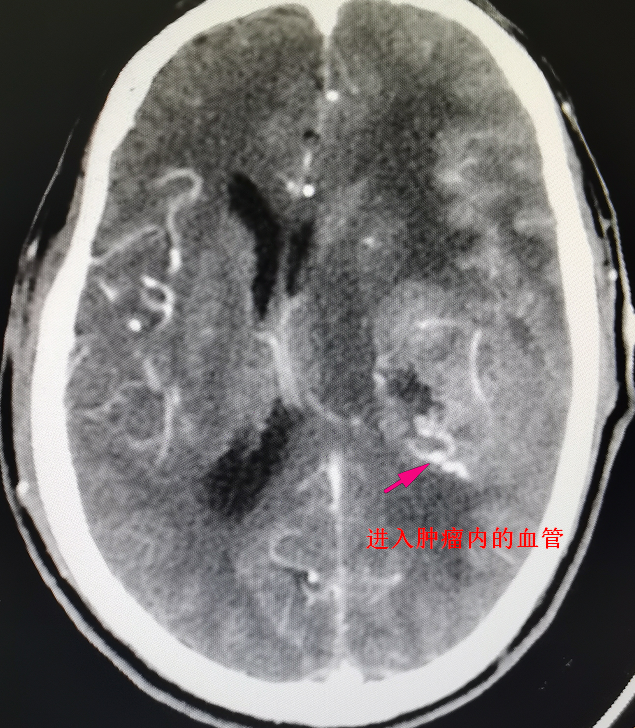

62岁的陈先生于今年曾因偏瘫在外院住院治疗无好转,且症状不断加重,甚至出现言语不清,小便失禁等异常。经影像检查(见图1)提示为左颞叶基底节区脑肿瘤,约6cm*5cm*5cm大小,比鹅蛋还要大,肿瘤位置深,向前累及外侧裂,包裹外侧裂部分血管,向下累及基底节区,肿瘤血供丰富,必须尽早实施手术治疗。

术前影像资料及手术标本,术前见中线结构严重偏移,侧脑室受压缩小,肿瘤周围水肿严重,肿瘤血供丰富

“由于肿瘤的位置侵犯外侧裂,影像学确定肿瘤包裹外侧裂的分支血管,有大脑中动脉以及枕动脉的多分支供血,紧邻肿瘤的还有过路血管。被包裹大的过路血管是不能损伤的,术中不小心损伤这段血管的话,大脑就会出现梗塞等一系列的并发症。”刘建民表示。